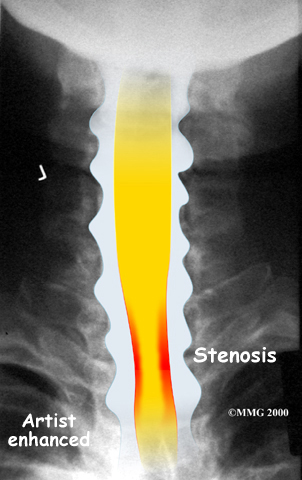

The bony spinal canal normally has more than enough room for the spinal cord. Typically, the canal is just less than ¾ of an inch, or 17-18 millimeters around, which is less than the size of a small bottle cap. Spinal stenosis occurs when the canal narrows to around half an inch, or 13 millimeters or less. When the size drops even further, severe symptoms of myelopathy occur. The symptoms of myelopathy result from the actual pressure against the spinal cord itself as well as the reduced blood supply in the spinal cord as a result of the pressure.

X-rays are used to look for the cause of pressure against the spinal cord. X-ray images can show if degeneration has caused the space between the vertebrae to collapse and may show if a bone spur is pressing against the spinal cord.